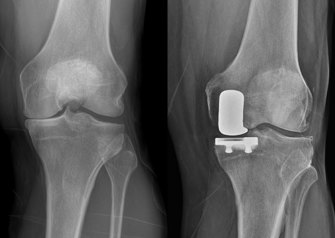

X-ray of partial knee replacement

Second opinions matter: Partial instead of full knee replacement

So, when pain in both of his knees began to affect his ability to sleep, comfortably work, ride a motorcycle, or do ordinary chores, he began to do his research. It was then that he learned that there were two types of knee replacement procedures: a total and a partial knee. Unlike a complete knee replacement, a partial knee replacement could be performed if only one part of the knee was affected by arthritis. He learned that potential benefits of a partial knee include a shorter recovery time, lower risks around the time of surgery, and a knee that feels more normal and natural since all of the ligaments are preserved.

“Mr. Corn was a good candidate for a partial knee replacement as he had arthritis predominantly on this inside of his knee, good flexibility, and normal-feeling ligaments,” Dr. Della Valle explains.